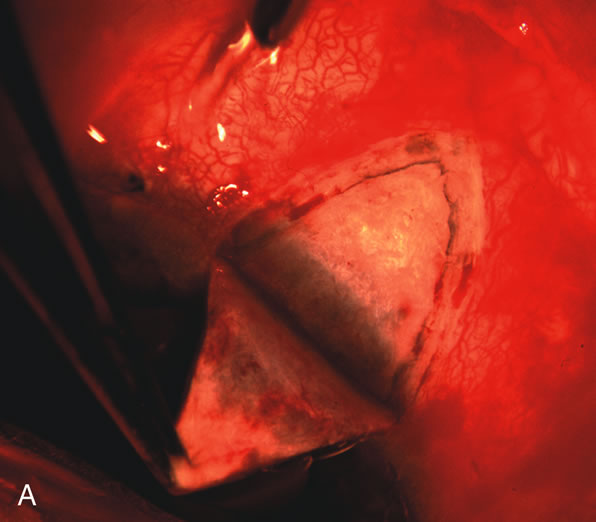

Fig. 7. Phacotrabeculectomy adjacent to a failed filter in cataractous eye. The ability to combine small-incision cataract extraction with trabeculectomy all through the same incision adjacent to the failed filter allows the surgeon to work in a familiar superior area. Avoiding incisions into the existing bleb decreases conjunctival buttonholes, hypotony, operating room time, and subconjunctival bleeding. A. Appearance of failed bleb with exposure of superior temporal quadrant gained with a corneal traction suture. B. Prepare a limbus-based conjunctival flap and a scleral flap. C. This bleb is at high risk to fail again justifying the need for MMC, 0.2 mg/cc applied on a pledget for 4 minutes. D. Insert the keratome and perform phacotrabeculectomy in the usual fashion.